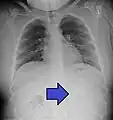

Gastrointestinal tract

One of the most common locations for a foreign body is the alimentary tract.

It is possible for foreign bodies to enter the tract from the mouth or rectum.